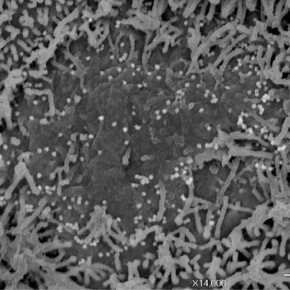

#Communiqué 🗞️ | Une étude internationale confirme la capacité du #SARSCoV2 à infecter les neurones et en identifie plusieurs conséquences. Les résultats ont été publiés le 12 janvier 2021 dans la revue Journal of Experimental Medicine. #COVID19 ➡️ cnrs.fr/fr/des-resulta…

#Communiqué 🗞️ |  Une étude internationale confirme la capacité du #SARSCoV2 à infecter les neurones et en identifie plusieurs conséquences. Les résultats ont été publiés le 12 janvier 2021 dans la revue Journal of Experimental Medicine. #COVID19